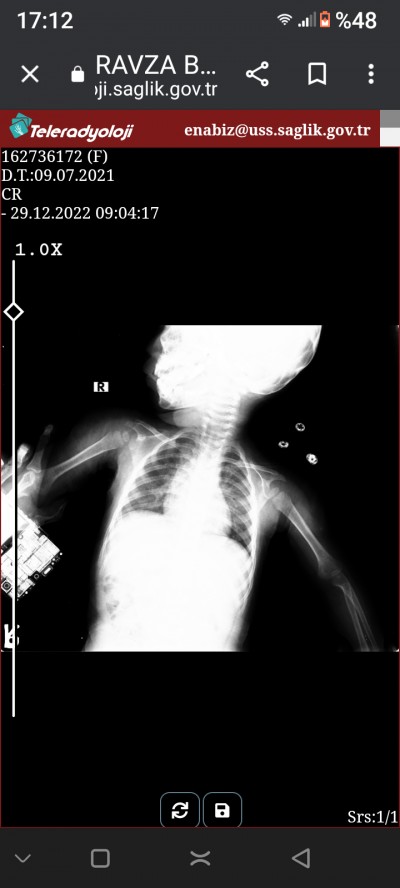

Kizlar bir buçuk yaşındaki kızımda öksürük vardı doktoro götürdüm akciyerde enfeksiyon vardedildi bu röntgen filminde beyaz yuvarlaklar var endişelendim belki anlayaniniz vardir

Rabbim şifa versin inşallah canım acaba üstünde elbisesiyle mi röntgen çektiler canım sanki bir düğme gibi bir şey var Allah korusun korkutmayın kendinizi iltihapta olabilir

Röntgeni bizim anlamamız çok zor. Bunun için en az 6 sene okuyor insanlar. İçinizi rahat tutun. Geçmiş olsun. O küçük yuvarlaklar da düğme gibi bir şey